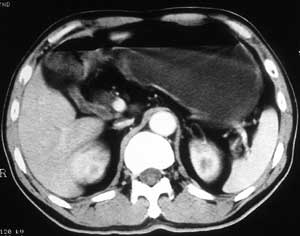

患者,男,57岁,梗阻性黄疸10余天。

这个病例胰头无明显增大,胆总管扩张明显而肝内胆管扩张更不明显,病程较短,

注意到十二指肠乳头明显突出,但尚光滑。分析以下可能性:

1、十二指肠乳头本身的病变,如乳头炎症;

2、急性乳头水肿,胆总管下端结石排石后乳头水肿;

3、壶腹部胆总管下端肿瘤累及十二指肠乳头。

十二指肠乳头粘膜慢性非特异性炎症